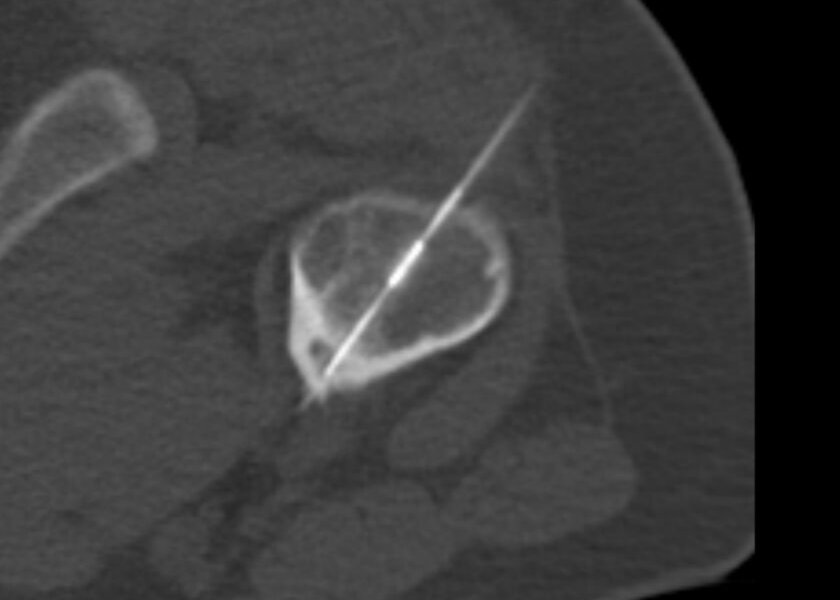

Neben den rein bildgebenden Verfahren werden am Institut für Diagnostische und Interventionelle Radiologie auch minimal-invasive Therapien durchgeführt. Dazu gehören unter anderem CT-gestützte Interventionen (zum Beispiel Entnahmen von Gewebeproben oder Radiofrequenzablationen von Osteoidosteomen) oder endovaskuläre Interventionen (zum Beispiel Embolisationen von Hämangiomen). In Kooperation mit der Nuklearmedizin werden auch die PET/CT und die Skelettszintigraphie angeboten.

Radiofrequenzablation eines Osteoidosteoms im Oberschenkelknochen